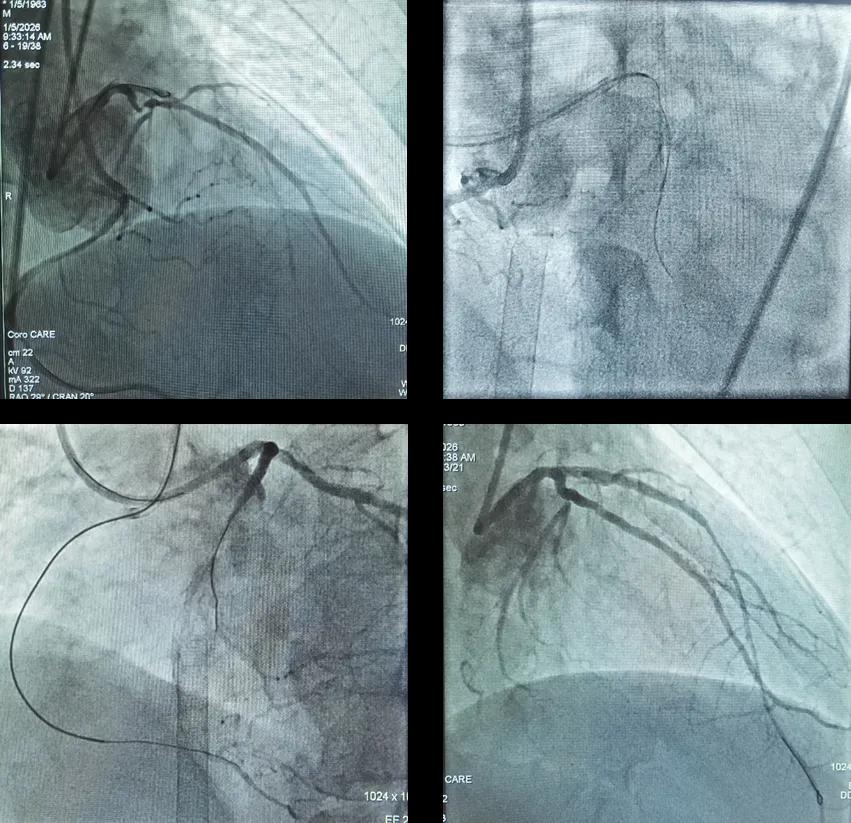

三支病变、双支闭塞,心脏射血分数仅剩10%!极危重心梗患者在河北医大二院重获“心”生

63岁的杜先生因“咽部紧缩感6个月,加重20天”入院。这个看似普通的症状背后,隐藏着一颗正在衰竭的心脏。 在心内一科,他被确诊为急性非ST段抬高型心肌梗死、慢性心力衰竭急性加重。患者心脏明显扩大,进一步的检查...